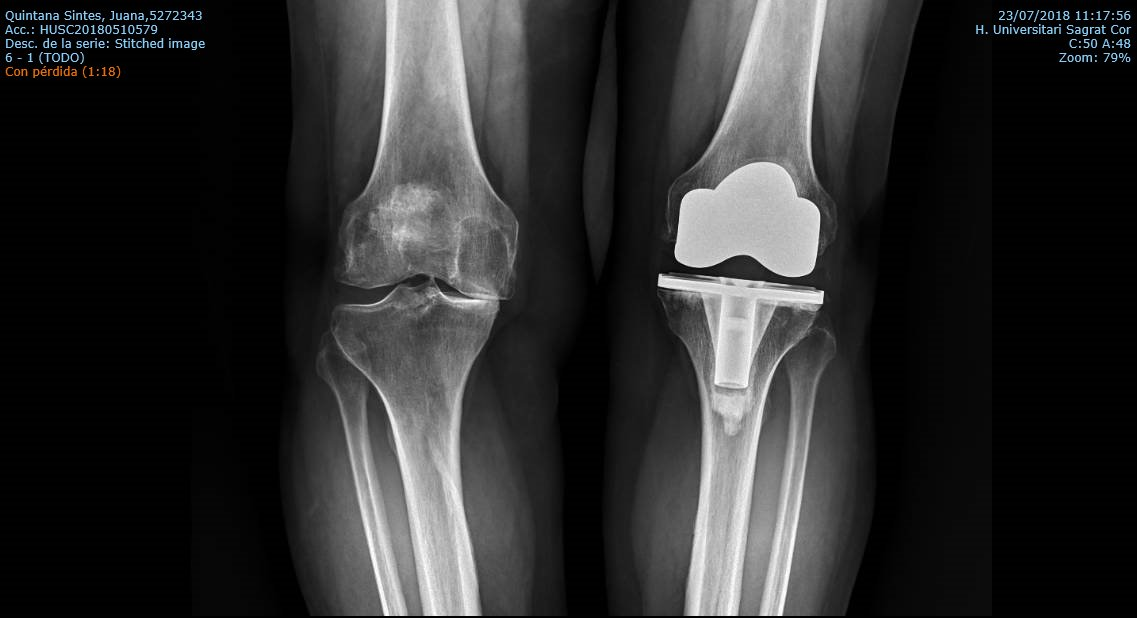

La prótesis total de rodilla es la cirugía más frecuentemente realizada para tratar la artrosis de rodilla. En una intervención con una historia de casi 50 años y es de las cirugías más exitosas que existen afortunadamente. Se realiza la sustitución del hueso desgastado mediante fijación de dos o tres implantes artificiales entre el fémur, la tibia y el fémur. Tras una minuciosa discusión con el paciente, el cirujano decidirá el tipo del implante a usar dependiendo de su edad, forma de los huesos (anatomía), nivel de actividad y calidad de hueso entre otros factores. Un minucioso estudio de planificación clínico antes de la cirugía permitirá la elección de los implantes que se requiere para adaptarlos y corregir la deformidad de la rodilla y de la pierna. Esa planificación hecha más habitualmente con radiografías permite elegir los implantes adecuados y prever los escenarios que pueden encontrarse en el quirófano – un paso imprescindible para el éxito de la cirugía. Los cirujanos de rodilla deben dominar un amplio repertorio de implantes para adecuarlo a cada situación. Los tres tipos de prótesis de rodilla son: la total, la unicompartimental y la femoropatelar.

La prótesis parcial de la rodilla es una prótesis especial que está indicado en pacientes con un desgaste muy inicial y con un patrón que afecta solo un compartimiento (interno o externo) de la rodilla. La unicompartimental medial es usada para desgaste entre el fémur y tibia por dentro y la unicompartimental lateral cuando el desgaste entre el fémur y tibia es por fuera. Tiene la ventaja de resecar mucho menos hueso del paciente, así preservando más hueso para el futuro. Además, al mantener la parte biológica del cartílago y la ligamentosa de los cruzados de la rodilla, parece conservar mucho mejor la sensibilidad y la marcha de la rodilla (la propiocepción). También la recuperación de esta cirugía (al ser menos agresiva) es más rápida.

Los mejores resultados de supervivencia se ven en pacientes con poca enfermedad y poca deformidad, mayor de edad o con normo/bajo peso. Los pacientes candidatos a esta protesis probablemente no son más de 5-10% del total de pacientes con artrosis de la rodilla. No obstante, su uso general es restringido debido a la probabilidad de la progresión de a enfermedad dentro del resto de la articulación, que puede ser generador del dolor y fracaso de la prótesis, con el paso de los años. Por tanto, cuando se decide por optar por este implante precisa un consenso claro entre el cirujano y el paciente entendiendo todos los variables que puedan surgir. Siempre que se plantea colocar una protesis parcial habitualmente también se tiene preparado la protesis total por si el grado de enfermedad comprobado durante la cirugía es más de la prevista antes de la cirugía.